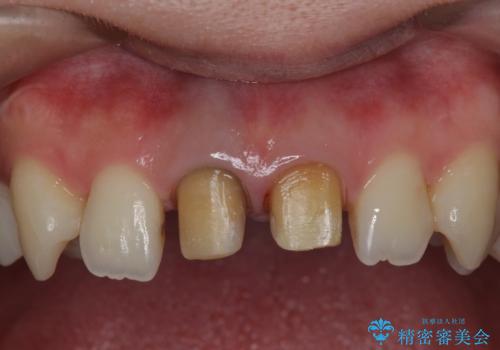

神経をとった前歯が変色してきた

- 昔に神経をとった前歯の変色が気になるとのことでした。

神経の方は問題なさそうだったため、患者様の希望でやりなおさず、土台とセラミック治療を行いました。

歯茎の黒ずみに関しては、中の歯の根が変色して透けている状態のため、変えることは難しいです。

笑っても歯肉が見えにくい方でしたので、問題ありませんでした。